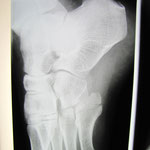

〇左前腕骨骨折(スミス骨折)

4件の整形外科をめぐり最終的に当院の保存治療を選択されました。

一件目の整形外科では足が専門なので断られシーネと包帯をしてもらいました。次に訪れた整形では手術が必要と大学病院を紹介

大学病院ではレントゲンの確認後、患部の手を触ることなく手術の日程を入れられました。手術に不安があった患者さんはインターネットで調べ手の専門整形外科を訪れました。そこでも手術を勧められ明日にでも処置をすると予定を強要されました。

しかし患者が不安を抱くのは手術だけではありません。どの医師も患部を診た触ることなしに当初巻かれた包帯のままでレントゲンを見るだけでした。そのため当初の包帯はぐじゃぐじゃ。たとえ手術の予定を入れたとしても包帯の巻きなおしが必要だったのではないでしょうか? これでは信頼できません。

当院はインターネットで知り来院されました。本人の強い意志と希望により当院で保存的に治療しています。経過は良好です。